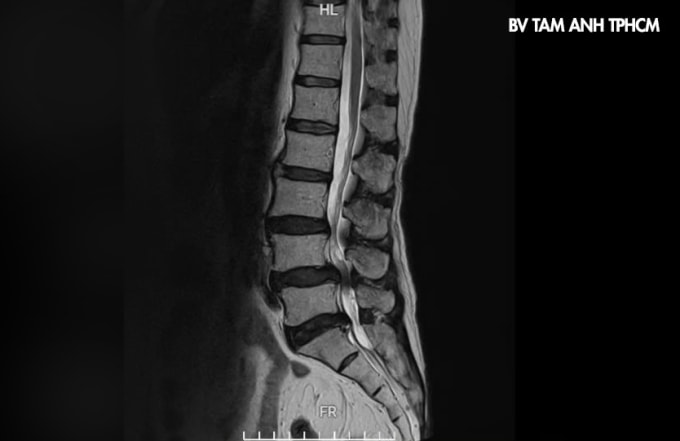

Nhiều trường hợp đau lưng cũng có thể là biểu hiện của các bệnh lý cột sống tiềm ẩn như thoái hóa cột sống, thoát vị đĩa đệm, hẹp ống sống, cong vẹo cột sống... Theo bác sĩ Thi, đây là những bệnh lý nguy hiểm, cần được khám và điều trị kịp thời, tránh nguy cơ phát triển các biến chứng, ảnh hưởng nặng nề đến sinh hoạt của người bệnh. Các triệu chứng thường gặp gồm:

Thoát vị đĩa đệm làm người bệnh đau âm ỉ vùng thắt lưng, lan xuống mông - đùi - cẳng chân, kèm tê bì, yếu chân.

Hẹp ống sống, trượt đốt sống đặc trưng bởi cơn đau tê kiểu điện giật, nóng rát; đau tăng khi vận động, giảm khi hơi cúi người hoặc ngồi nghỉ.